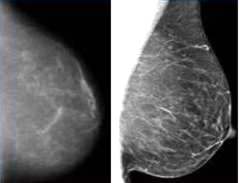

Al respecto consultamos al profesional que atendió a Clara por esta situación, y éste explicó que pidió a la paciente hacer una placa en Judais porque las del hospital Samic son muy borrosas (algo que notamos con facilidad), y es imposible hacer un diagnóstico con las mismas… “sería adivinar” dijo. En cambio las hechas por el instituto privado son totalmente nítidas, bien visibles.

La diferencia está en el revelado. En el SAMIC de Oberá todavía se revelan las placas “a la antigua”, en un cuarto oscuro y bajo un foco rojo, cosa que ya no se usa más hace tiempo en la medicina moderna. En cambio las hechas en Judais son DIGITALES.

La diferencia de nitidez en las placas se nota, una es borrosa y la otra parece HD.

Esto quiere decir que hace apenas dos años se compró con dinero del ESTADO (todos) un mamógrafo tanto para el SAMIC de Oberá, como otros tres para San Vicente, Alem y Puerto Iguazú que serían iguales; pero que no sirven porque el revelado es de manera arcaica y otorga imágenes borrosas ergo, no confiables y por lo tanto no solo pueden generar angustiosos falsos positivos, si no que además obligan a tener que recurrir al sistema privado de salud, y el que no tiene obra social ni plata para pagarlo, queda a la deriva de la salud pública.

imagen ilustrativa que muestra diferencias entre Mamografía borrosa como se hace en el SAMIC comparada con la mamografía digital moderna